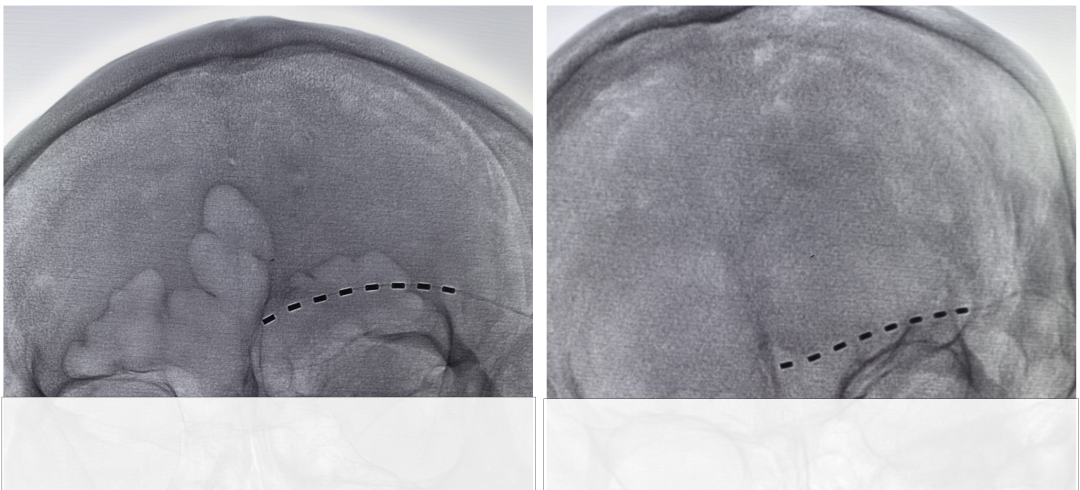

近日,山东大学附属威海市立医院疼痛科顺利为两名长期受神经痛困扰的老年患者实施了眶上神经电刺激植入术,显著缓解了患者的疼痛症状,标志着医院在面部难治性神经病理性疼痛的微创诊疗领域再上新台阶。两名患者均为老年人,曾患额面部带状疱疹,疱疹愈合后仍遗留额部三叉神经支配区剧烈疼痛。疼痛表现为烧灼样、电击样、刀割样,并伴有频繁、突发、难以控制的爆发性剧痛。患者自述“痛不欲生”,因持续疼痛和频繁发作,昼夜无法入睡,不敢睁眼,不敢触碰额部,同时伴有焦虑、抑郁情绪,生活质量严重受损。患者此前曾先后接受镇痛药物、中医中药、神经阻滞等常规保守治疗,疼痛均未得到有效控制,遂慕名来市立医院疼痛科就诊。科室专家团队对患者进行系统、细致的评估后,决定采用眶上周围神经电刺激微创植入术进行靶向镇痛治疗。

周围神经电刺激(Peripheral Nerve Stimulation, PNS)是目前国际公认的微创、可逆、可调、非毁损性神经调控镇痛技术。本两例患者的病变主要累及眶上神经支配区,眶上周围神经电刺激具有靶向性强、安全性高、疗效确切的优势,尤其适用于高龄、基础疾病多、难以耐受高风险治疗的老年患者。手术在局部麻醉下进行,经皮微创穿刺将微小电极精准植入眶上神经走行区域,通过低频温和的电刺激调控痛觉神经传导通路,阻断异常疼痛信号上传,从而抑制神经病理性疼痛及爆发痛。该术式不损伤神经、不破坏组织,患者术中保持清醒,创伤小、恢复快。经过规范的程控治疗,患者剧烈的电击样、烧灼样疼痛明显减轻,爆发痛发作频率及程度显著下降甚至消失。患者能够安稳入睡,正常睁眼活动,触碰额部不再引发剧痛,焦虑情绪明显缓解,日常生活逐步恢复正常。